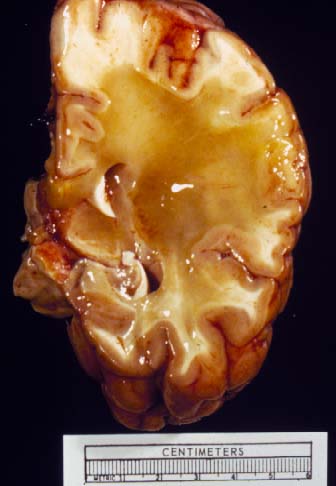

Gross Photo

Gross Photo: This gross photo was taken from a different case. Note that the white matter is diffusely replaced by a yellow gelatin like substance.